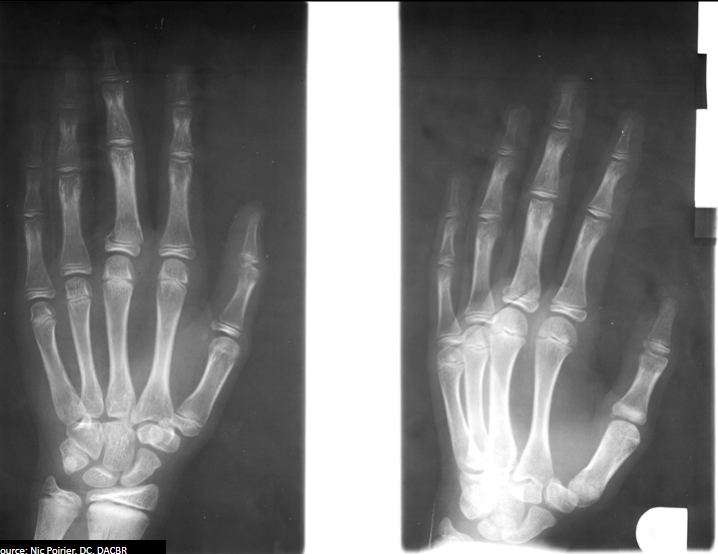

Q

What type of fracture is demonstrated?

A

Comminuted

How well did you know this?